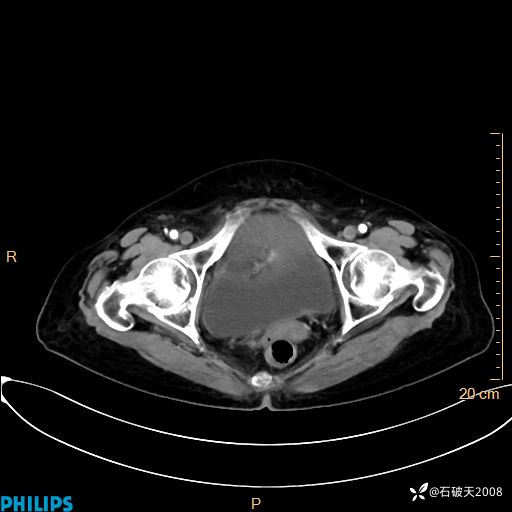

动脉期